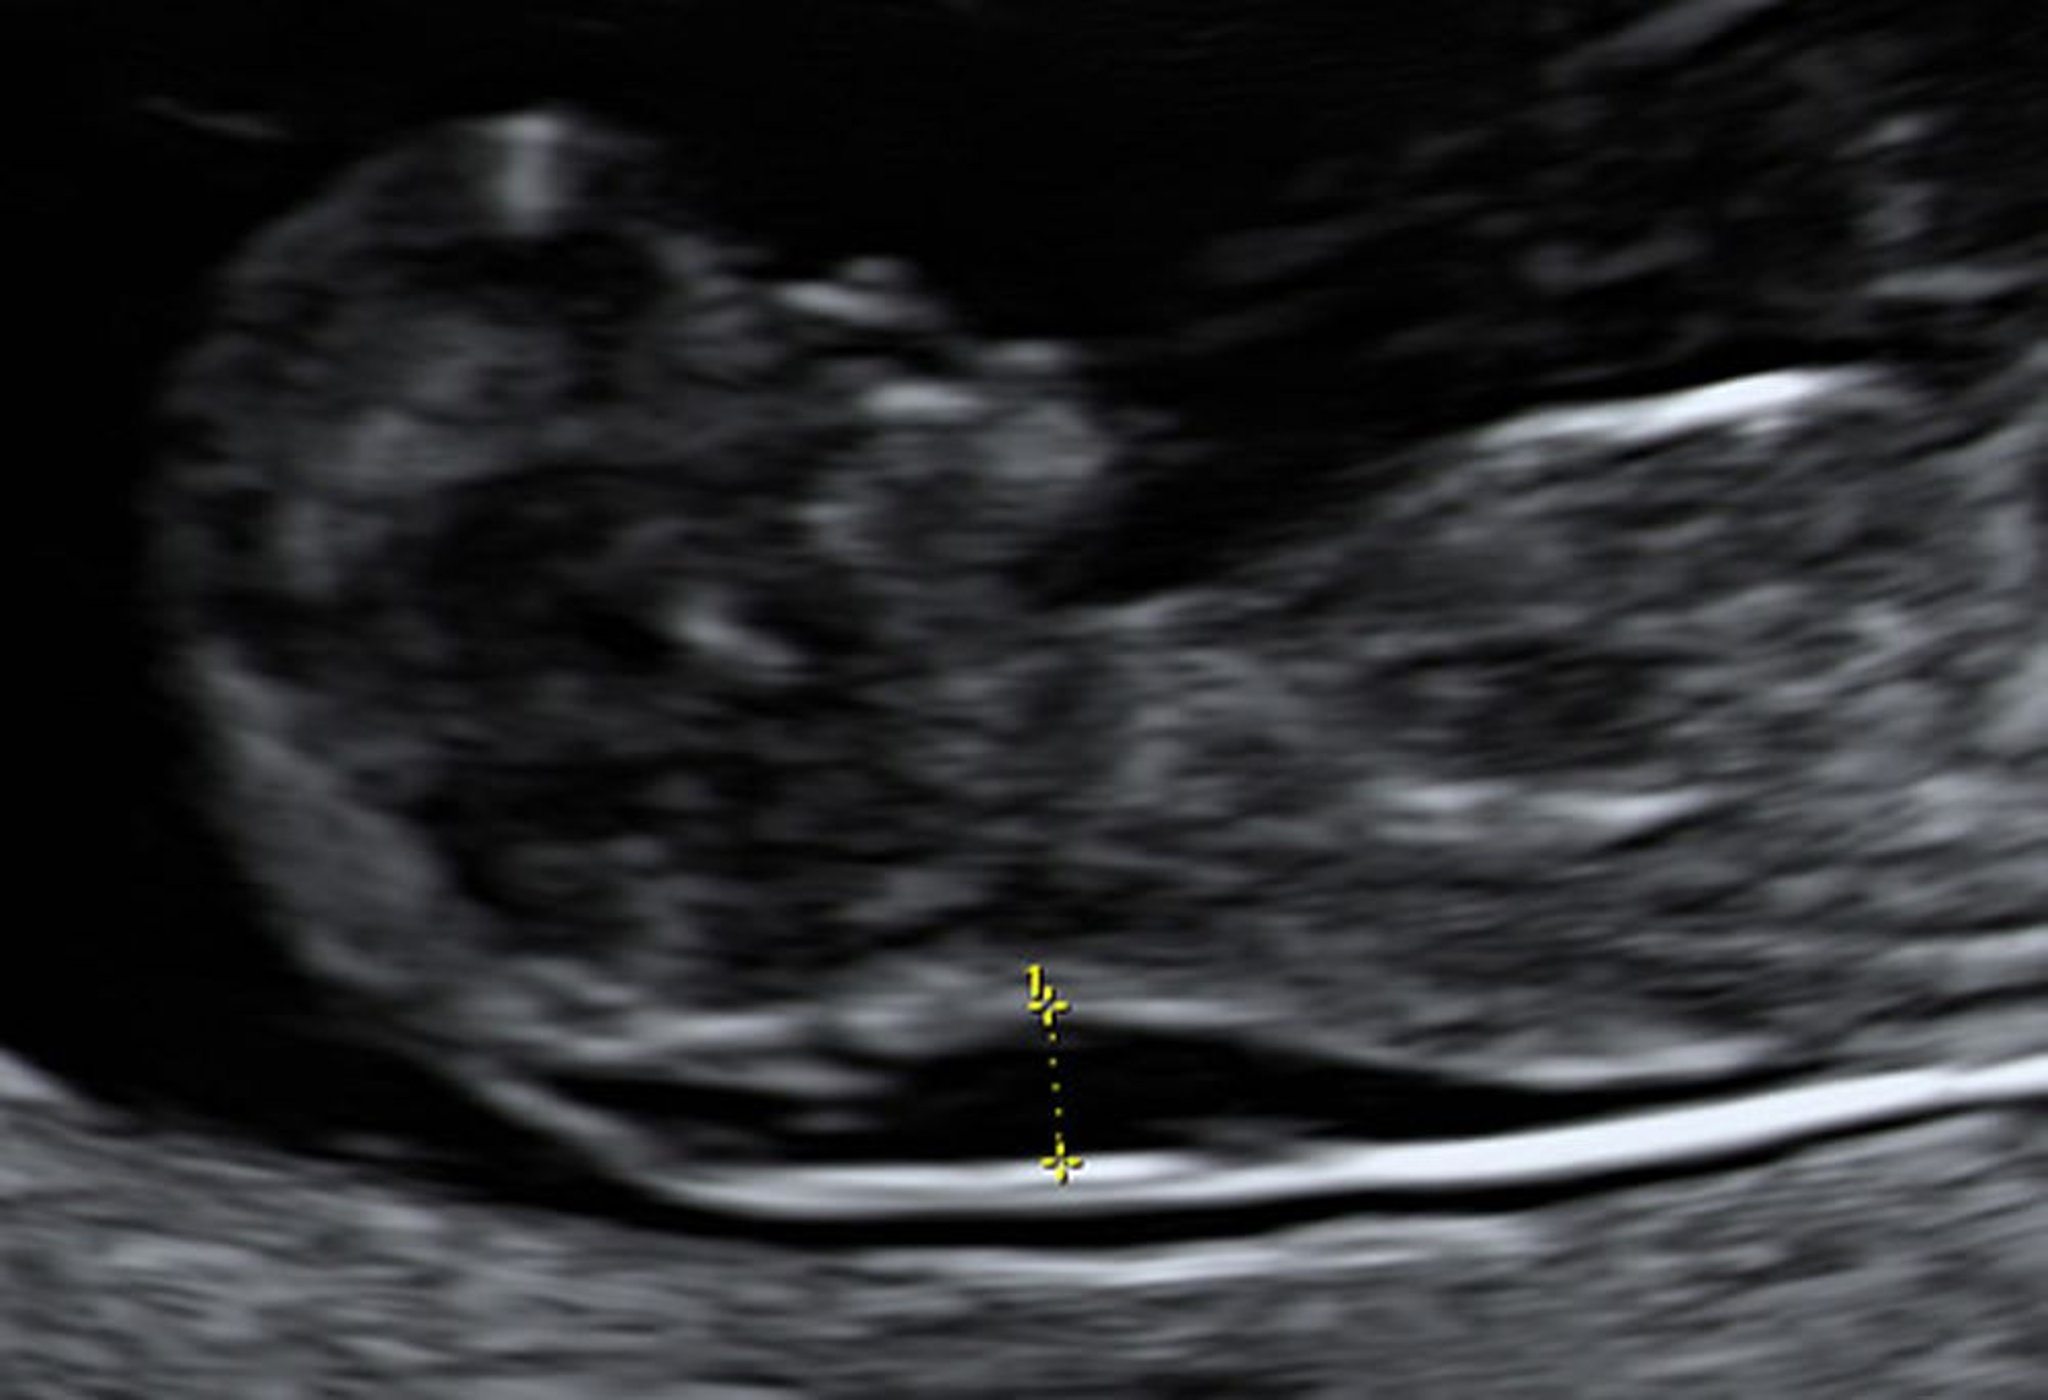

Ultrasonografia che mostra una traslucenza nucale ingrandita in un feto di 10 settimane

Il campionamento dei villi coriali ha indicato che questo feto aveva la sindrome di Down.

Photo from Jeffrey S. Dungan, MD.